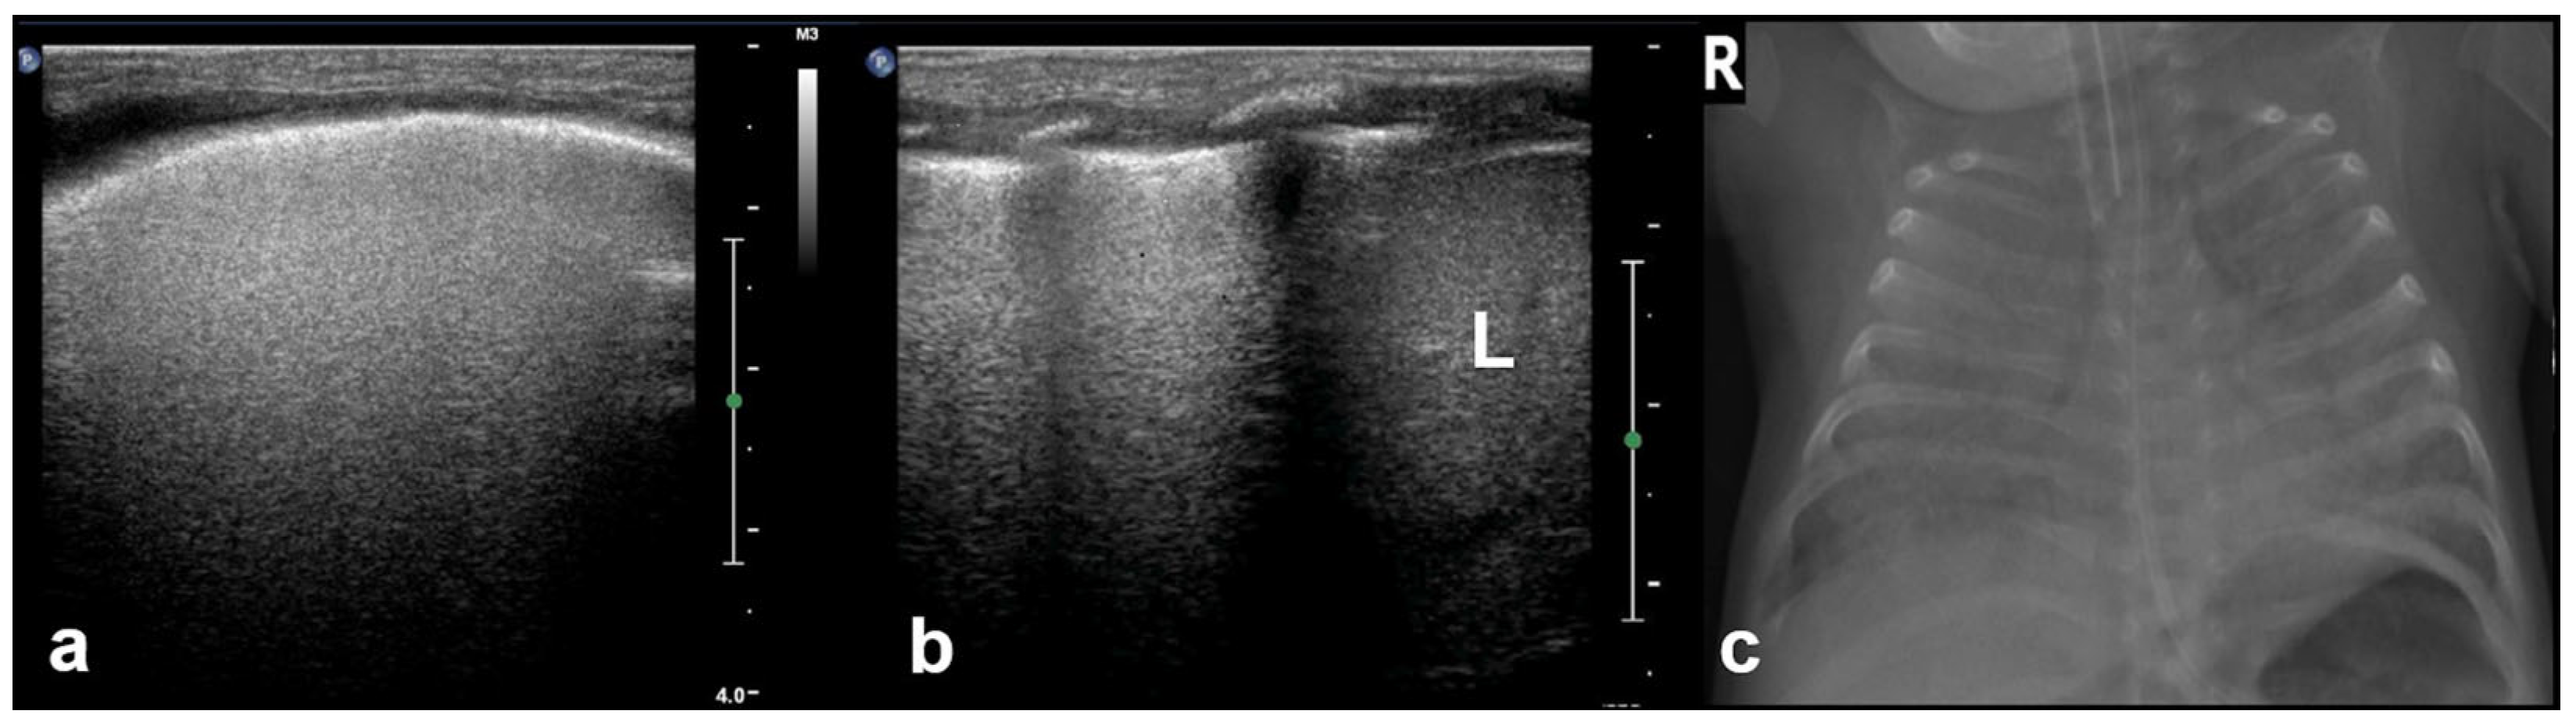

3.2.10. Pleural Effusion

Pleural effusion, defined as the accumulation of fluid in the pleural space, can be easily detected by LUS, which is highly sensitive and able to identify even small volumes of fluid (as little as 5–20 mL). In contrast, effusions greater than 175–250 mL must typically be present for the detection of pleural effusion by conventional chest X-rays, although lateral decubitus views may detect effusions of approximately 50 mL. A pure pleural effusion typically appears as an anechoic collection located between the parietal and visceral pleura, often seen as a clear, dark space (fluid) that allows for the visualization of underlying lung structures and diaphragm movement [13,20,35,54].

In contrast, complicated effusions may exhibit internal echogenicity due to the presence of fibrin, debris, or infection. Identifying the nature of the effusion, in other words whether it is simple effusion or complicated, is critical for clinical decision-making, and may help indicate the need for drainage, antibiotic therapy, or surgical intervention. Thus, LUS can be considered to play a pivotal role in both the diagnosis and management of pleural effusions, particularly in neonates and critically ill patients [10,23].

3.2.11. Empyema

Empyema refers to the accumulation of purulent material within the pleural space, typically as a complication of pneumonia or other infectious processes involving the lungs. In neonates and pediatric patients, empyema is a significant cause of morbidity and often presents with respiratory distress, fever, and signs of pleural effusion. LUS is a valuable tool for the evaluation of empyema, because it often offers greater sensitivity than chest X-rays and can be used to effectively guide both diagnosis and management [6,12,54].

LUS findings in empyema typically reveal a complex pleural effusion rather than a simple anechoic collection. The effusion often contains internal echogenic debris, fibrinous strands, and multiple septations that create a multiloculated appearance. These features help differentiate empyema from uncomplicated effusions. In some cases, the adjacent lung may appear consolidated, and pleural thickening is commonly observed. The consolidated lung adjacent to the empyema may show reduced or absent air bronchograms, reflecting impaired ventilation due to compression or infection.

Timely recognition of pleural empyema is critical, because it requires aggressive intervention, including antibiotics and often image-guided or surgical drainage. Thus, lung ultrasound not only facilitates early detection of pleural empyema, but also plays a crucial role in procedural planning, monitoring therapeutic response, and reducing reliance on ionizing radiation in vulnerable pediatric populations (Figure 23) [6,12].

Figure 23.

Pleural effusions.